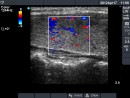

Follow-up examinations (rows from 1st to 8th):

Corresponding sonographic images (row)

2. Note the relation between volume, echogenicity, vascularization and hormone levels.